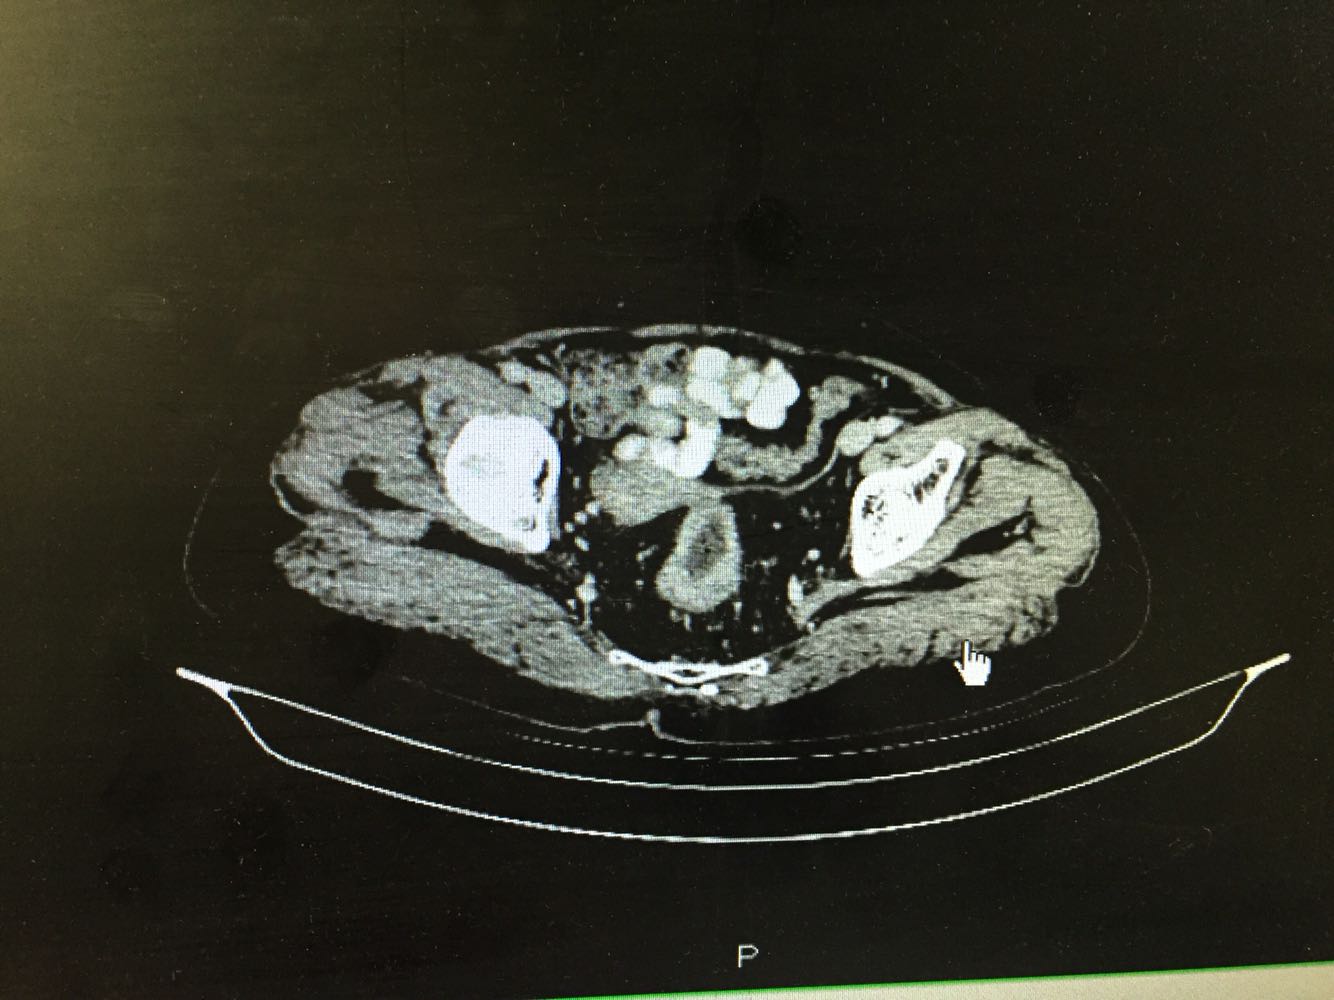

直肠指诊 距肛门7cm可及肿物下缘,环周生长,质偏硬。初诊直肠癌。病理提示高级别上皮内瘤变,未见平滑肌,浸润癌不排除。 腹部CT证实局段直肠癌厚,占位可考虑。

直肠占位明确,考虑活检深度不够,认为直肠癌可能性大。与患者家属商议后同意直接手术。行腹腔镜下直肠癌根治术。手术顺利,恢复满意。

患者病史比较长,一直未处理及治疗。术前阅片考虑外周侵润不明显,遂行腹腔镜手术,术后病理提示侵及深肌层,肠周淋巴结18枚均未见转移。 如果患者当初有症状及时就诊,可能并未癌变。基层见太多晚期肿瘤患者了。看病贵还是问题。